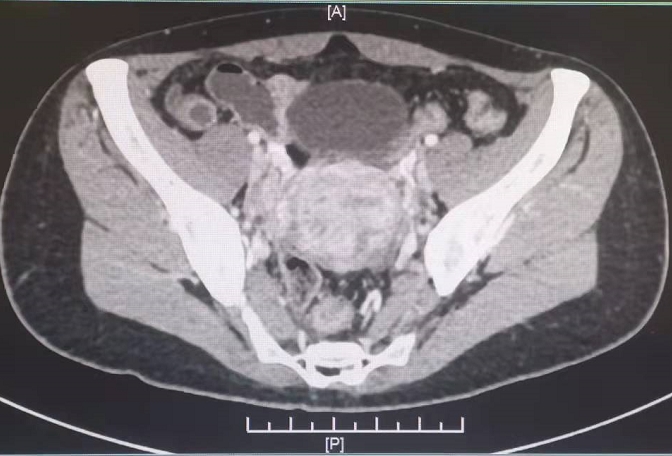

重医二院·医事快讯91丨宫内节育环移位,女子子宫、直肠壁被穿破!医生检查发现还有更严重的问题……